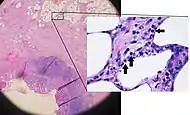

Pathology

Even for clinically certain appendicitis, routine histopathology examination of appendectomy specimens is of value for identifying unsuspected pathologies requiring further postoperative management.[69] Notably, appendix cancer is found incidentally in about 1% of appendectomy specimens.[70]

Pathology diagnosis of appendicitis can be made by detecting a neutrophilic infiltrate of the muscularis propria.

Periappendicitis (inflammation of tissues around the appendix) is often found in conjunction with other abdominal pathology.[71]

Micrograph of appendicitis and periappendicitis. H&E stain

Micrograph of appendicitis and periappendicitis. H&E stain Micrograph of appendicitis showing neutrophils in the muscularis propria. H&E stain

Micrograph of appendicitis showing neutrophils in the muscularis propria. H&E stain Acute suppurative appendicitis with perforation (at right). H&E stain

Acute suppurative appendicitis with perforation (at right). H&E stain